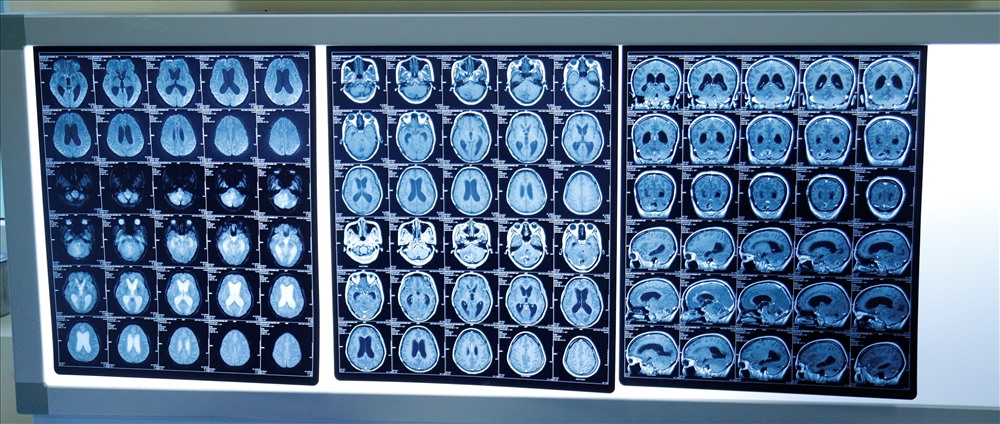

Hình ảnh u não của chị H. Ảnh: VOV. |

Chia sẻ trên báo Tuổi Trẻ, bác sĩ Nguyễn Đức Liên - trưởng khoa Ngoại thần kinh Bệnh viện K - cho biết khi vào viện bệnh nhân đã có 3 ổ di căn ở não, đặc biệt di căn vào hố sau gây chèn ép, dẫn đến tình trạng hôn mê. Các bác sĩ đã quyết định dùng thiết bị xạ phẫu điều trị trong 3 đợt cho bệnh nhân, do e ngại điều trị 1 đợt thì sức khỏe bệnh nhân không đảm bảo.